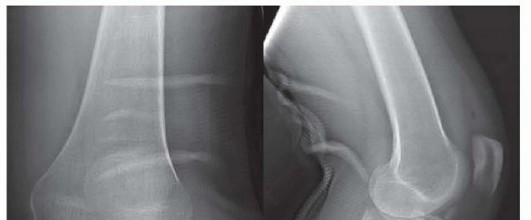

k DEFINITION A direct approach with the patient in a prone position to the posterior aspect of the tibial pla…